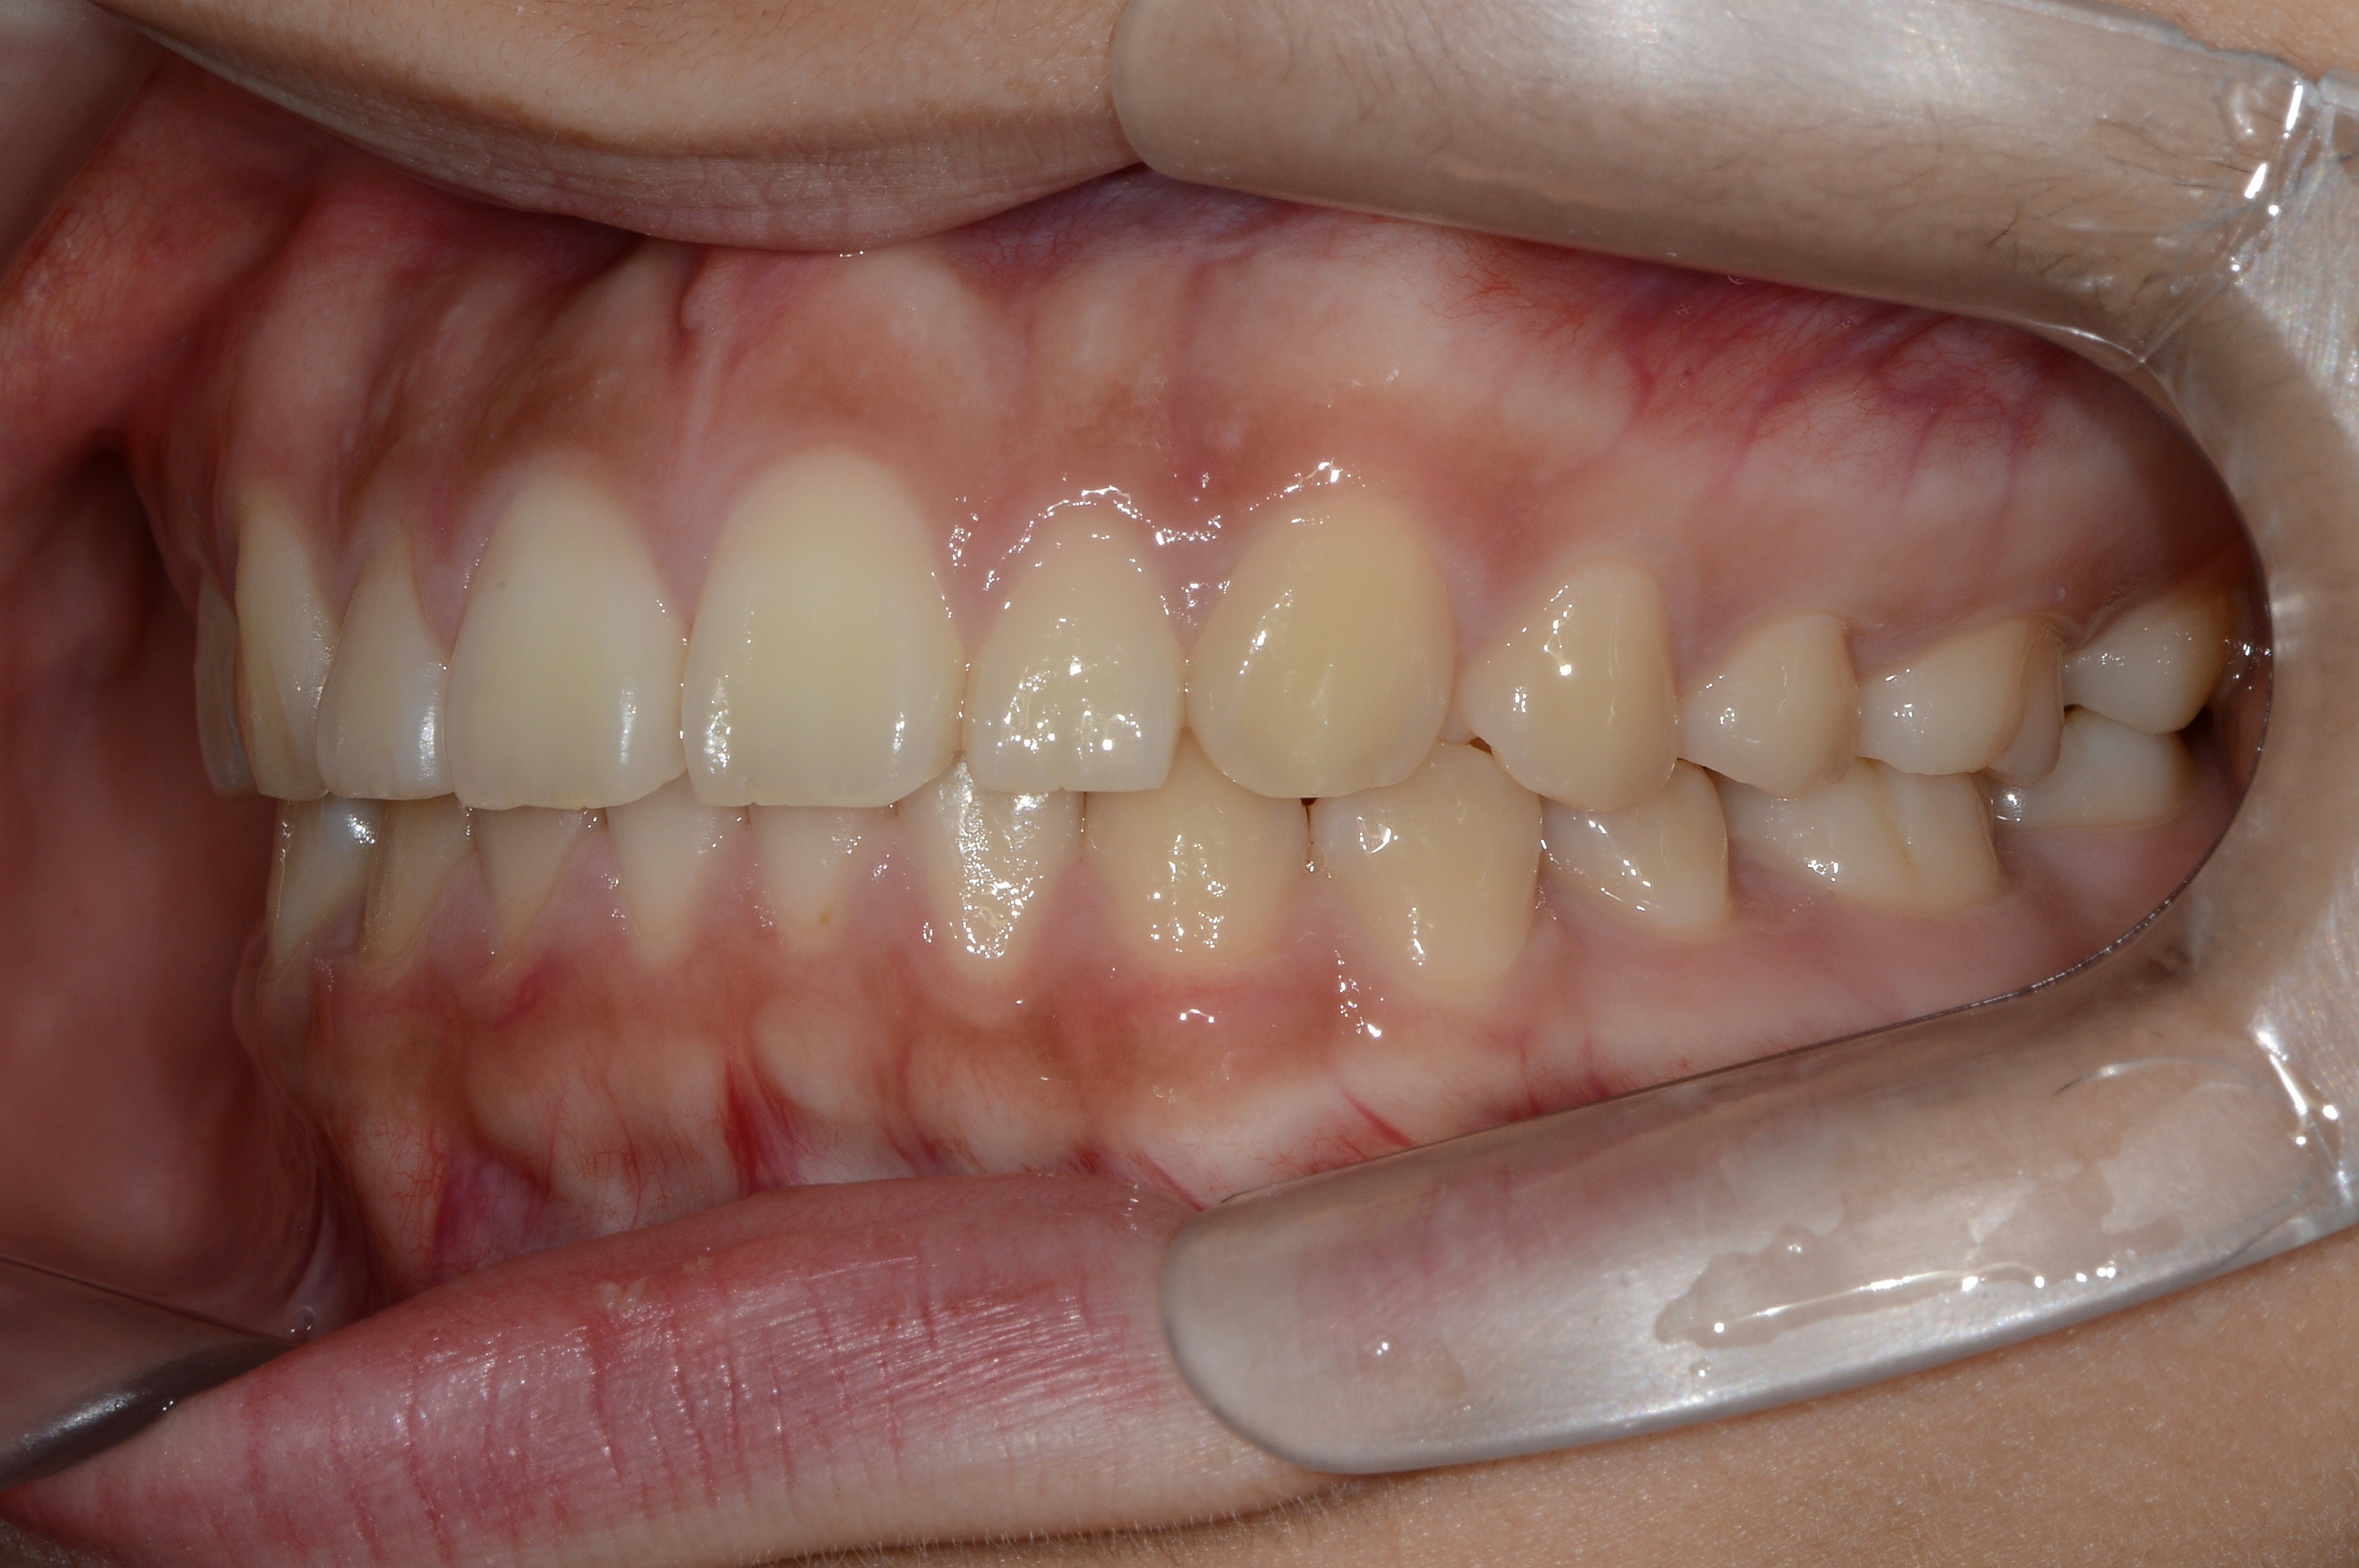

치료 후 사진입니다.